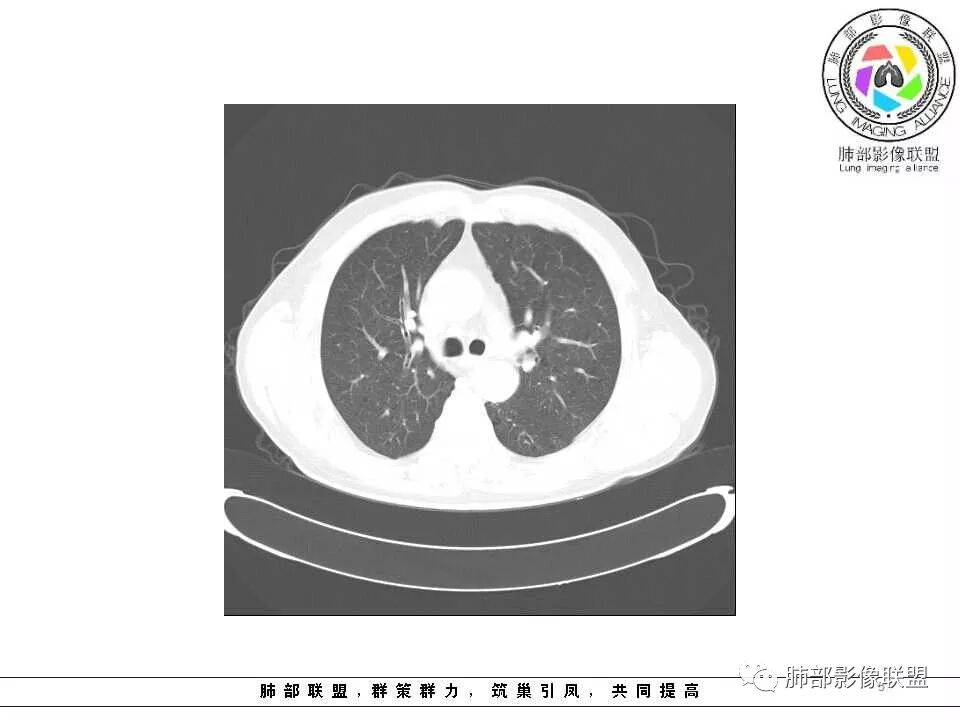

影像学特点:肺气肿背景下在大概一年的时间里出现了一个光滑的小结节,因为图像给的不是太薄,与支气管的关系判断不清,从结节周围出现斑片状炎症来判断,应该考虑结节位于支气管内,周围是阻塞性炎症,这样比较容易解释咯血

左肺舌段条片状实变影,边界较清楚,形态不规则,平行于支气管,其内可见支气管扩张,考虑炎性病变(OP,结核,NTM)鉴别:淋巴瘤

老年男性,左肺舌段见多个小结节灶及斑片状高密度灶、磨玻璃影,结节灶边界清晰,光滑,无明显分叶,密度均匀,周围病灶密度不均,一年内生长,考虑恶性肿瘤并阻塞性肺炎出血,小细胞可能大。

老年男性,肺气肿基础。约一年时间出现左肺上叶舌段支气管近端结节影,远端斑片样阴影,边缘模糊。考虑近端恶性占位,远端有阻塞性炎症。

老年男性,有咳血病史,左肺上叶舌段一年时间出现新发类圆形小结节,感觉在支气管内,部分凸出气管外,没有mpr不好说,远端肺野斑片模糊影,考虑阻塞性炎症,纵隔无明显肿大淋巴结,小细胞代排,按照发展速度,类癌低度恶性,应该发展缓慢,一年病史,代排,首先考虑鳞癌并阻塞性炎症

肺气肿背景,2016年左肺上叶上舌段见微结节,2017年5月左肺结节增大,密度均匀,边缘光滑锐利,与邻近血管关系密切,血管贴壁走行,外侧见尖状突起,下舌段片状影,沿着支气管走行,内有粘液栓,考虑鳞癌,鉴别小细胞肺癌。

肺气肿背景,2016年左肺上叶上舌段见微结节,一年后左肺结节增大,密度均匀,边缘光滑、膨隆,似见小分叶,下舌段片状影,沿着支气管走行,内,老年患者,咯血1月。考虑恶性病变并阻塞性肺炎,鳞癌?注意鉴别结核。

左肺上叶舌段支气管管壁略增厚 间隔一年 管壁增厚明显 向腔外突出形成结节 管腔闭塞 远端片状及斑片影 纵隔淋巴结增大 肺气肿背景 考虑鳞癌伴阻塞性炎症可能

老年男性,咯血1月,肺气肿背景,16年左肺上叶舌段结节,左肺门疑似淋巴结肿大,呈结节感。17年左肺上叶舌段见沿支气管走行分布结节 远端阻塞性肺炎,左肺门淋巴结肿大明显,首先考虑恶性病变,鳞癌?类癌?

前次片2016年4月20相应位置就有小点状病灶,2017-5-15呈结节影改变,边界膨隆,远端阻塞炎性改变,考虑肺癌,鉴别炎性结节!